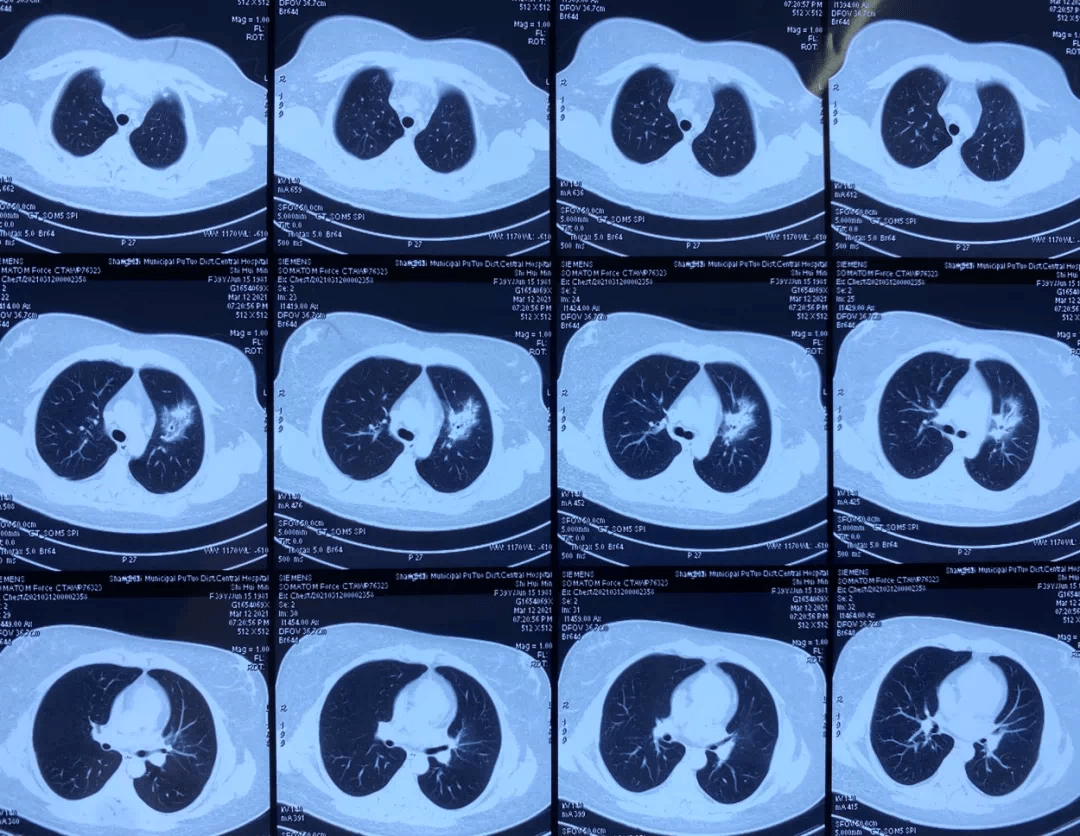

曾抱著貓吸聞毛髮,發燒至 40℃、怕冷、打寒戰 上海 39 歲的於女士 (化名) 萬萬沒想到,去寵物店聞貓後,竟然高燒不退,最後住進了上海長征醫院呼吸與危重症醫學科。 經過精準檢測發現,導致於女士發熱的元兇竟是鸚鵡熱衣原體。醫生提醒,從疾病預防的角度來說,不建議聞貓,這種行為容易導致經口和呼吸道的病原體感染。 ![]() 鸚鵡熱屬於人畜共患病,所有的哺乳動物都會傳染。 之所以叫鸚鵡熱是因為最初該病是一種發生於鸚鵡類鳥中的衣原體病,主要通過一些病鳥或死鳥所產生分泌物攜帶的病毒感染,然後被攝食或呼吸吸入而引發此病。 對於免疫力低、頻繁接觸鳥類的人要注意。購買活禽時要與活禽保持距離,在食用禽類時要將其徹底煮熟。 ![]() |